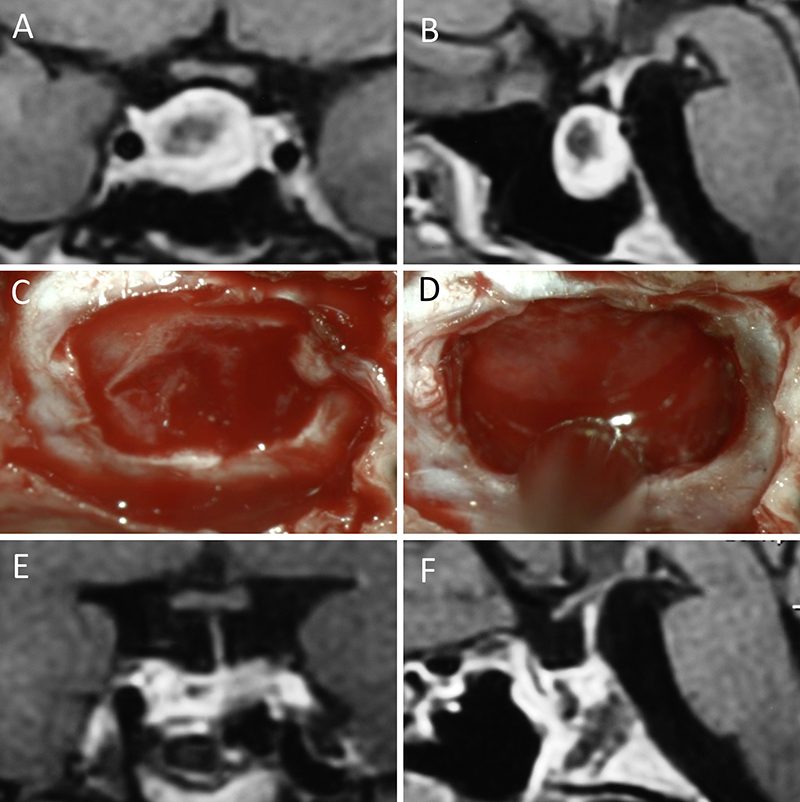

Figura 3: Macroadenoma no funcionante en un hombre de 64 años. El paciente presentó en el preoperatorio déficit visual que mejoró tras la cirugía. A-B: RM preoperatoria; C-D: intraoperatorio; E-F: RM postoperatoria.

Figura 4: Macroadenoma no funcionante en mujer de 32 años. La paciente presentó en el preoperatorio déficit visual que mejoró tras la cirugía. A-B: RM preoperatoria; C-D: intraoperatorio; E-F: RM postoperatoria.